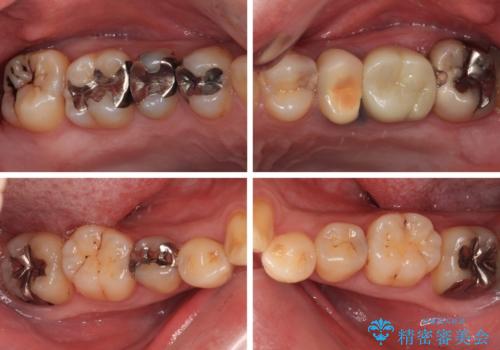

- 銀歯やむし歯でものが挟まるところが気になるとのことで来院された患者様です。

その他は銀歯のインレー(部分的な詰め物)が装着されており、それらはむし歯を除去した後にセラミックインレーにて修復治療を行い、左下と根管治療を行う左上の奥歯はオールセラミッククラウンにて補綴治療を行うこととしました。

目立っていた銀歯がなくなり、患者様には大変満足していただけました。